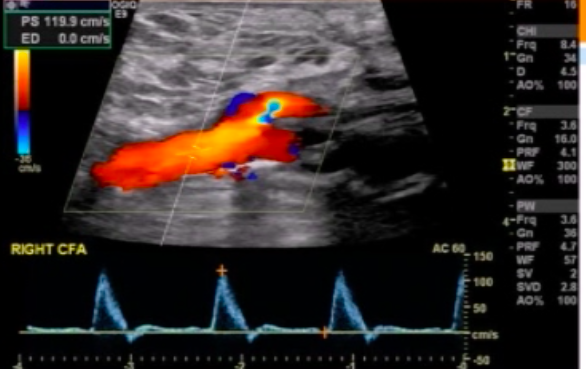

Pt undergoes LE arterial DUS. Interrogation of CFA is shown below.

Most important finding to report?

patent CFA-graft anastamosis